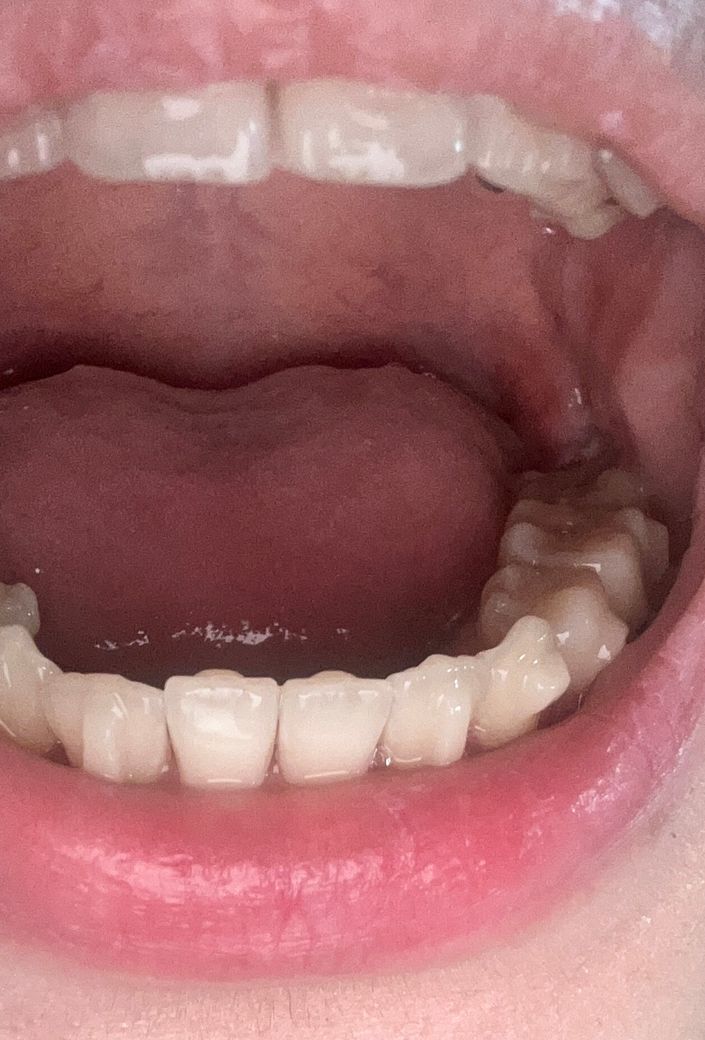

사랑니 발치 일주일 됐는데 실밥이 안 보여요..

잇몸이 살로 덮히면서 실밥이 하나도 안 보여요..제거못하면 어떡하죠

괜찮은 거 맞나요..? 그리고 일주일 지났는데도 아직 턱 쪽이 욱신해요ㅠㅠ안녕하세요. 김지훈 치과의사입니다.

실밥이 붓기등에 의해서 잇몸에 파 뭍혔을 수 있습니다. 사진 상에선 염증 등의 문제는 보이지 않습니다.

사진상으로 보면 발치한곳이 잘 아물고 있는거 같습니다. 실밥은 떨어져 나갓을수도 잇고 안보여도 잇몸에 덮혀잇어도 제거가 가능하니 걱정하지마세요.

발치후 잇몸이 자연스럽게 치유되면서 실밥이 숨겨져 안보이는 경우가 있으나 녹는 실인 경우에는 문제가 되지 않습니다. 만약 그렇지 않은 경우에도 치과에서 조치를 취할수 있기에 걱정하지 않아도 되며, 치과 진료시 점검을 받길 권합니다.

사진으로도 보이지 않기는 합니다만 간혹 실 전체가 다 풀리거나 잇몸이 약간 찢어지면서 실이 통째로 탈락되어 삼키는 경우가 있습니다. 치과에서는 보다 자세하게 관찰할 수 있기 때문에 크게 걱정은 안하셔도되고 통증은 아직 일주일이라면 조금 있을 수는 있습니다.